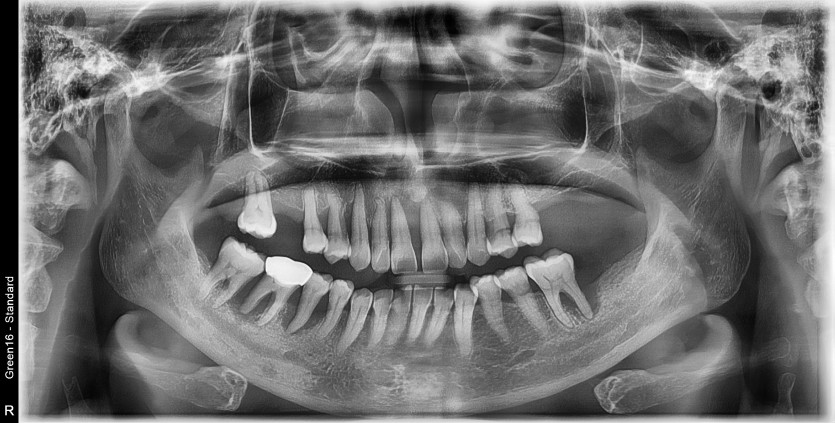

만 52세 상악 전체 임플란트 증례(하악 일부)

상악 전체 임플란트 증례입니다.(하악 일부)

14개의 임플란트로 완성하였습니다.